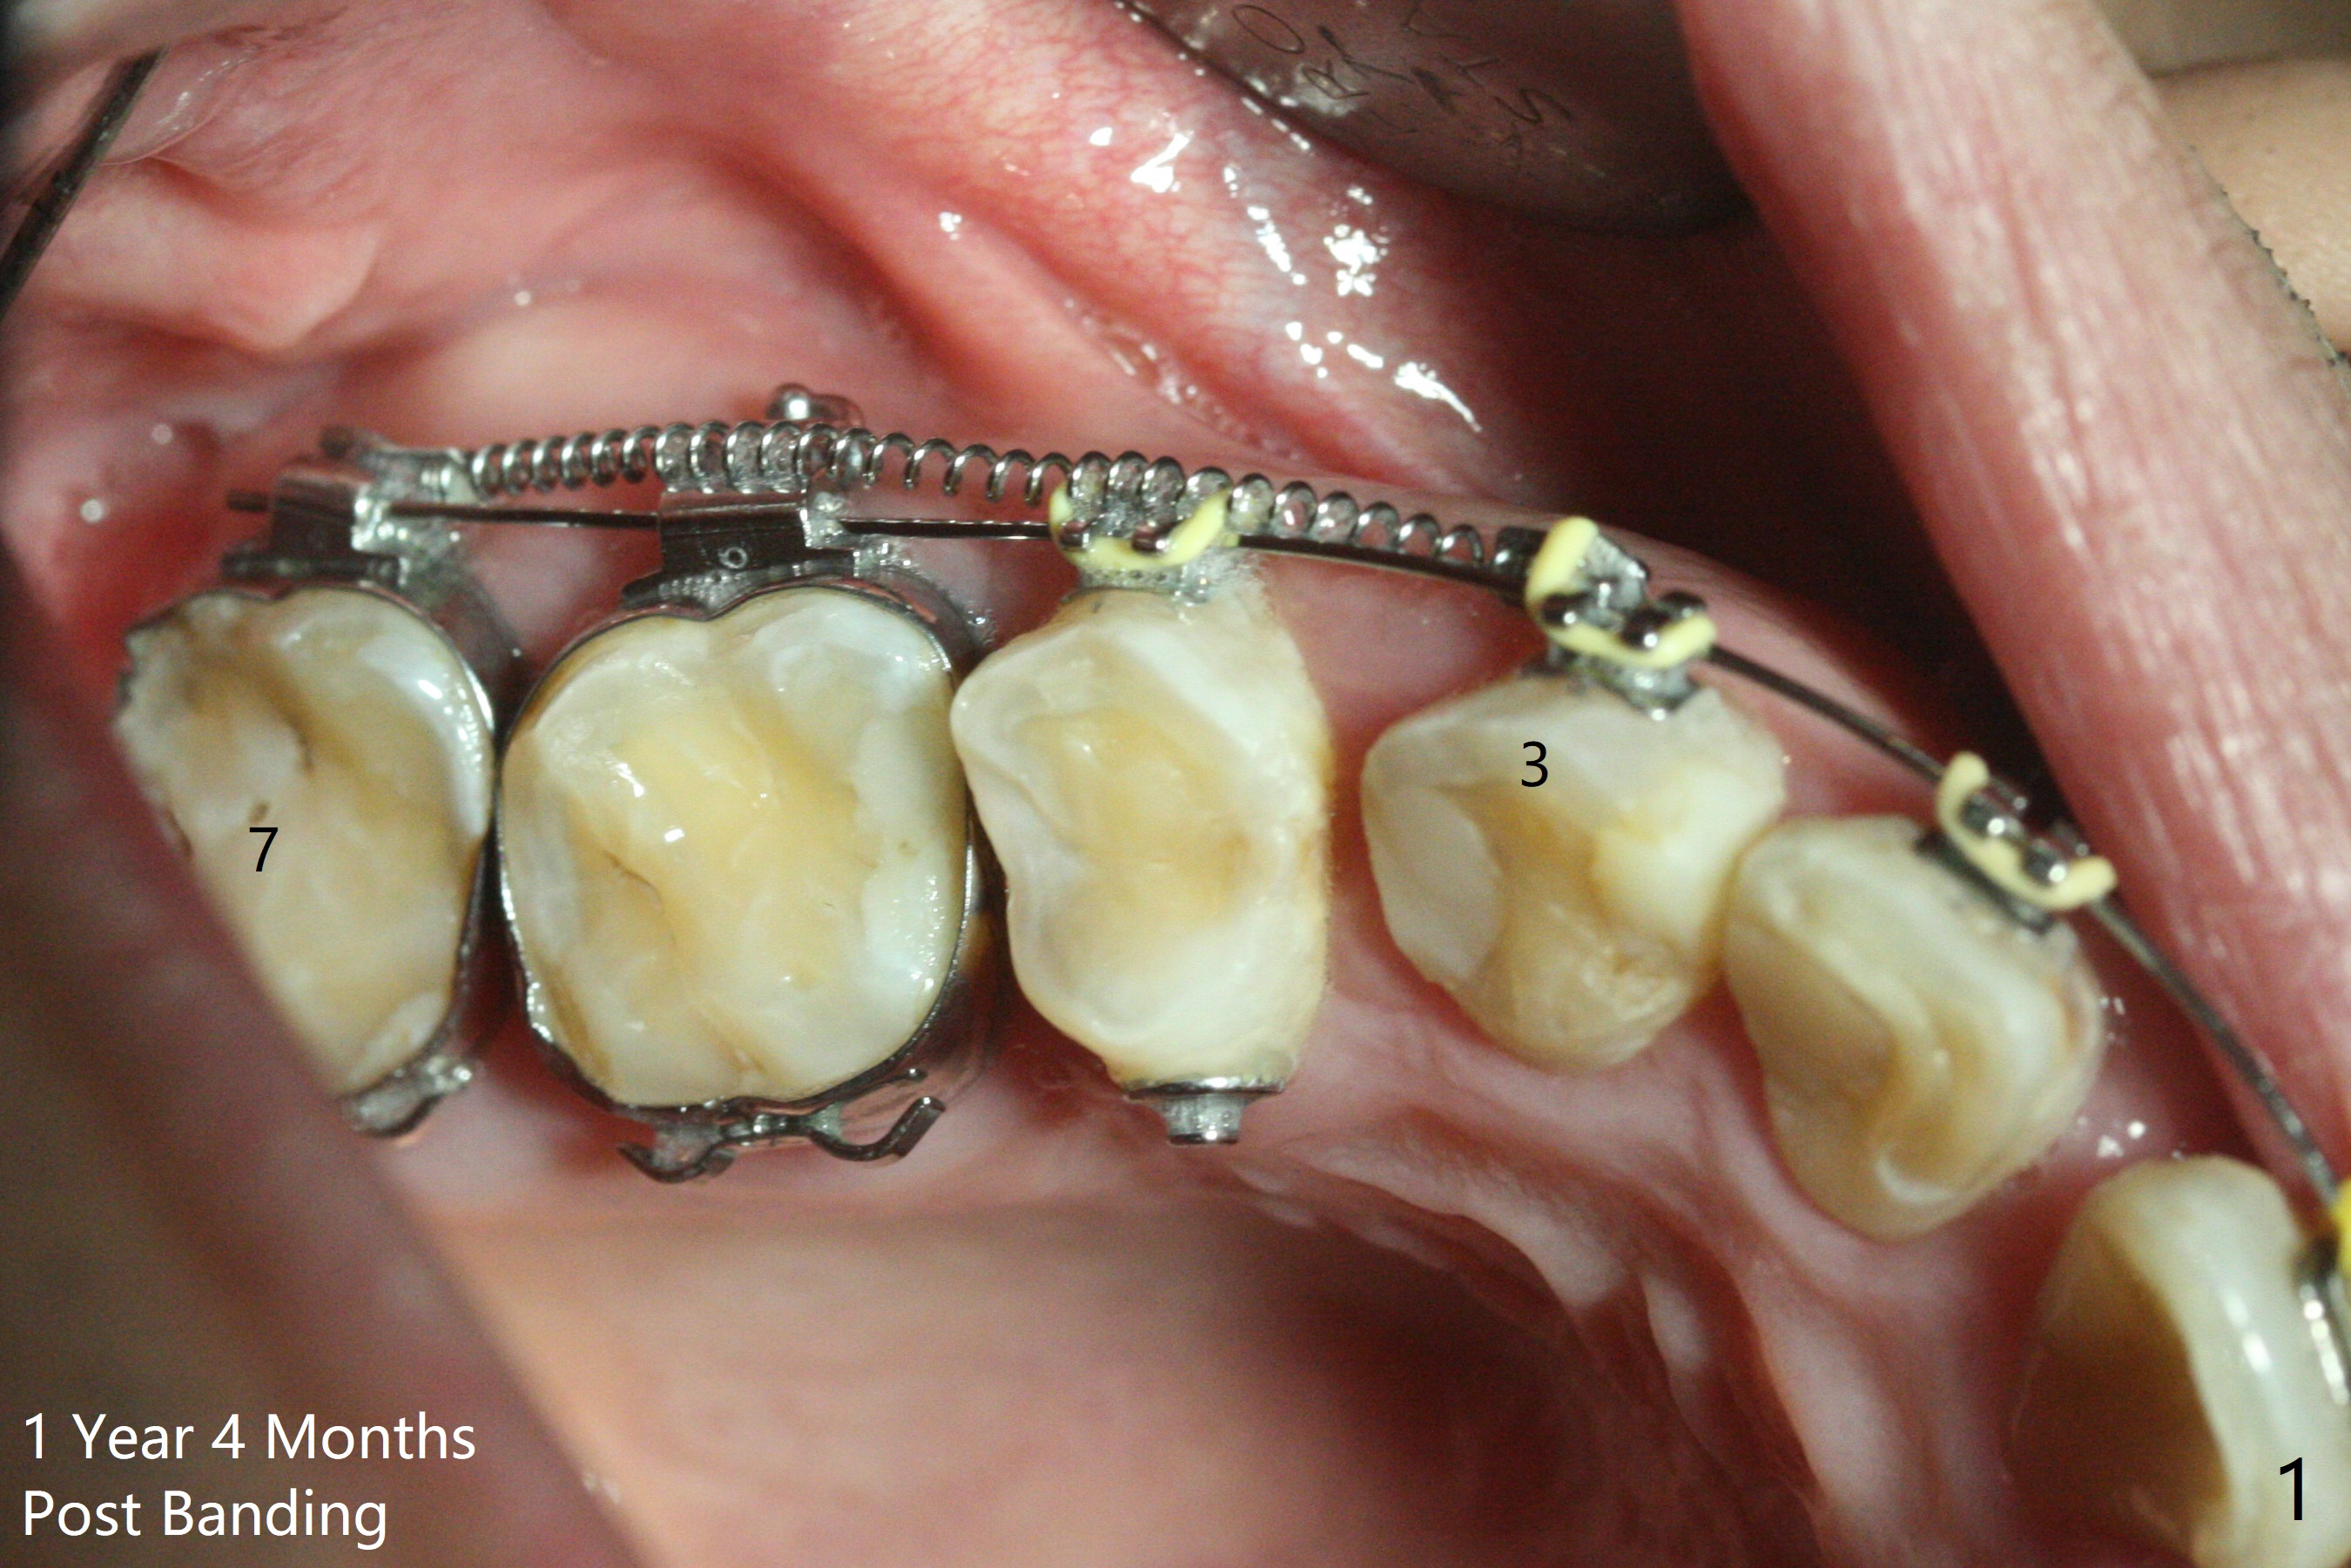

One year 4 months post banding (M) with 16x16 wires, UR3 is being distalized using UR7 as anchor (Fig.1), while the upper dental midline matches the facial one (Fig.2). The anterior overjet remains large (Fig.3). When UR3 is fully distalized, place posted wire to distalize U2-2 together. U2-2 distalization seems to be slow with one 16 mm closed coil spring each side (between 7 and post) 1 year 10 months post banding. Since the upper anterior PA shows mild root resorption at UR2 (Fig.4), a 14 mm closed coil spring is added each side (between 6 and post, Fig.5,6). LR6 has pain 2 years 2 months post banding (Fig.7). Debridement confirms non-salvageability; a 5x11.5 mm implant will be near the mesial root (Fig.8). Power chains for a month leads to closure of the gap between 3 and 4 (Fig.8-11). The space between 4 and 7 is 15 mm. A 12 mm 1st molar crown will be made, while the remaining 3 mm space will be closed by mesialization of 7 using 2 power posts mesial and distal to 6 and 7. Draw 2 tubes of blood. Make an incision to expose the mesial crest of 6.